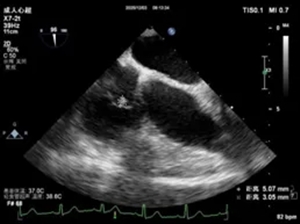

经食道超声三尖瓣隔瓣

赘生物